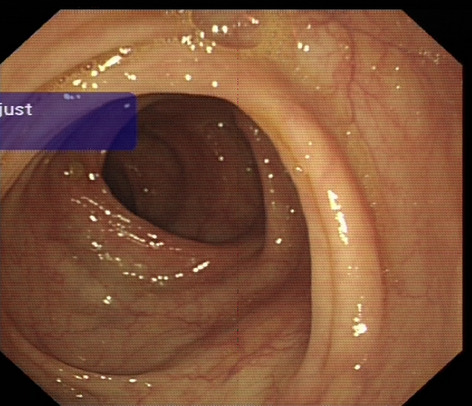

The primary therapeutic modality for colorectal cancer is surgery. Although oncologically effective, a persisting dreadful complication of surgery is anastomotic leakage. Despite the multi-factorial origin, the general consensus is that an important factor is the state of microcirculation at the site of the anastomosis, which cannot be assessed with the naked eye. Lapvas-Imaging is a contactless, dye-free imaging modality that gives instantaneous and continuous real-time insight in the state of bowel perfusion during laparoscopic surgery. The medical device is based on a technique called laser speckle contrast imaging and works plug-and-play with standard commercial laparoscopes. This study aims to determine whether the use of additional Lapvas-imaging derived visual feedback might influence the surgeon’s choice for the location of the anastomosis.

In this prospective, observational, multi-center trial, patients undergoing an oncological colorectal resection were included. 2D-perfusion maps were generated from images taken with Lapvas-Imaging (LIMIS Development BV, Leeuwarden, The Netherlands) in combination with a standard surgical laparoscope and video system (EndoEye, Olympus Medical, Hamburg, Germany) during surgery, before the creation of the proximal and distal anastomosis. The images were shown to the operating surgeon and non-involved surgeons postoperatively.

In this ongoing trial, 16 patients with oncological colorectal resections were included. No medical device related adverse events were observed. Images reveal anastomosis made in well-perfused tissue (Fig. 1A) as well as on the border of poor-perfused tissue (Fig. 1B). Lapvas-Imaging could instantaneously visualize the perfusion and discriminate well- and poor perfused bowel with only 3 min 6 s average added surgical time (Fig. 2A). Preliminary results show that operating surgeons would have changed the anastomosis in 39% (Fig. 2B) of the patients, with an average of 1.2 cm. One patient developed anastomotic leakage that was indicated for a change in location based on Lapvas-Imaging.

Preliminary results show that the bowel perfusion can be real-time visualized using standard laparoscopic video systems in conjunction with Lapvas-Imaging. Furthermore, the 39% indication of change in clinical decision-making could indicate that surgeon’s value the added perfusion information. Patient inclusion will be continued and updated results will be presented to evaluate its potential for bowel perfusion imaging.